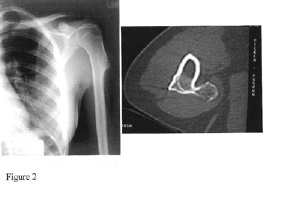

Osteochondromas of the arm are often readily felt but rarely cause neurologic dysfunction.

(Figure 2). Osteochondromas of the upper extremities frequently cause forearm deformities. The prevalence of such deformities has been reported to be as high as 40-60%. Disproportionate ulnar shortening with relative radial overgrowth has been frequently described and may result in radial bowing. Subluxation or dislocation of the radial head is well-described sequelae in the context of these deformities.